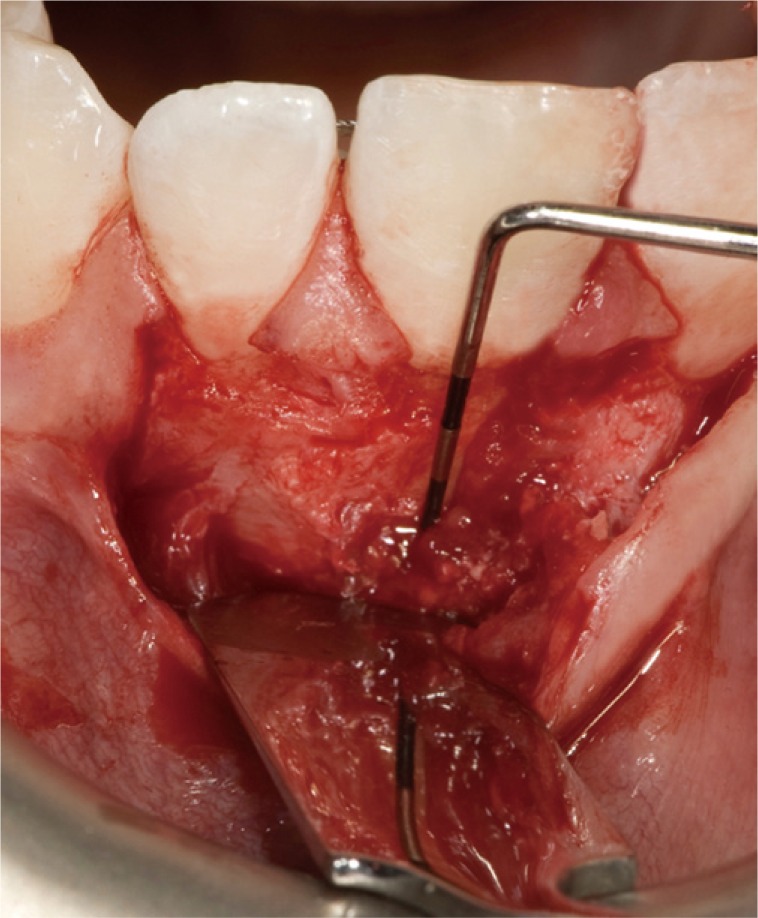

A clinical examination showed a moderate swelling on the vestibular side in the region of tooth #21, as well as the presence of a sinus tract in the same area, approximately 4 mm from the gingival margin (Figure 1). A narrow periodontal defect 7 mm in depth was present on the buccal side, as evaluated using a periodontal probe. A radiographic examination performed before surgery using both periapical radiographs and CBCT (J. Morita MFG Corp., Kyoto, Japan) revealed a root-end resection, a periapical radiolucency, and a widening of the periodontal ligament space at the mesial aspect of the root, although no hair-like fracture line radiolucency was noted in the tooth, except in the CBCT horizontal projection that showed an incomplete VRF 3 mm from the apex (Figure 2).